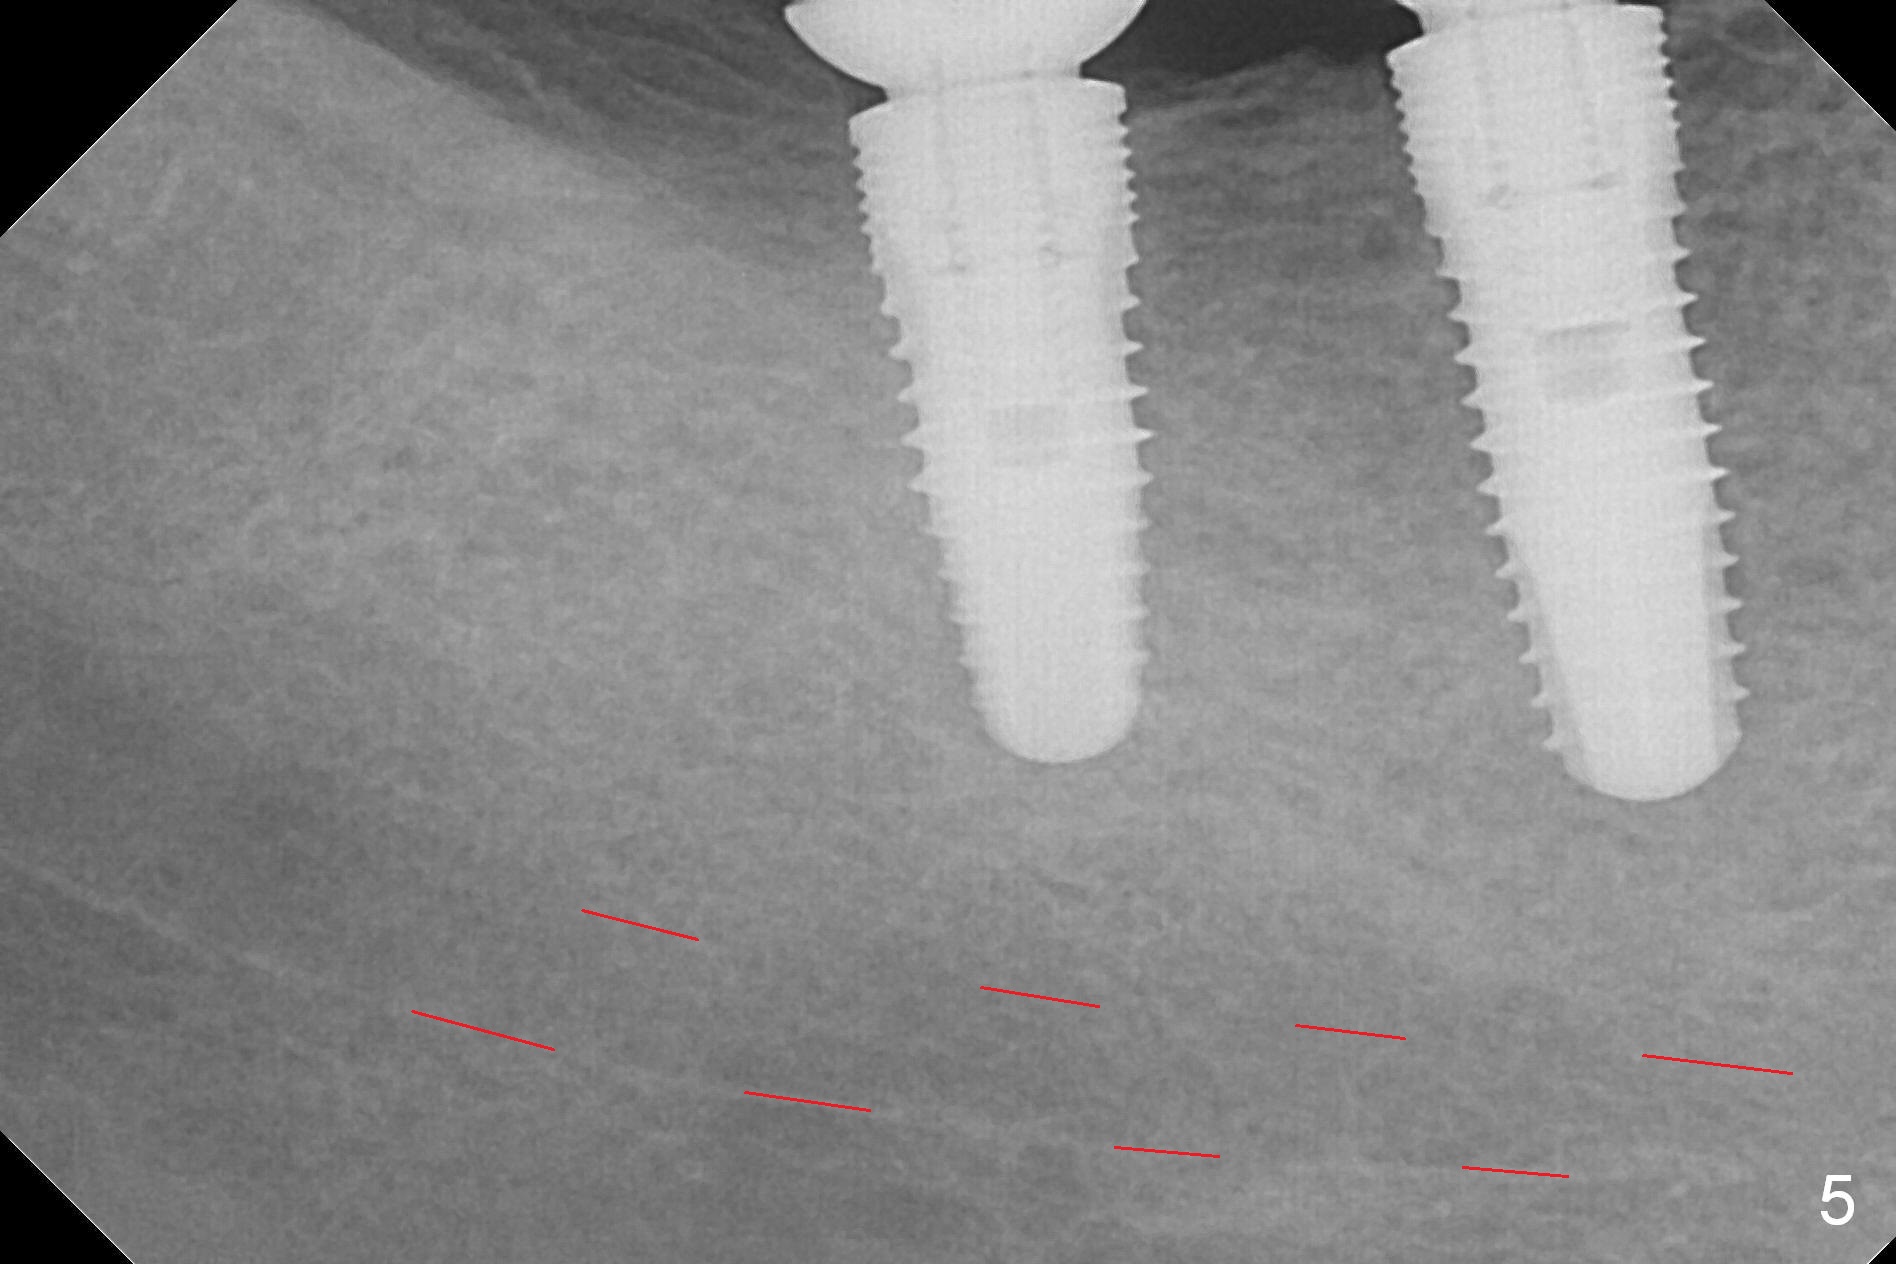

The supraerupted tooth #2 is adjusted using the lower right surgical stent.  Osteotomies are initiated by using starter drill through surgical stent over the ridge (Fig.1) prior to incision.  The initial depths are 10 and 12 mm at the sites of #31 and 30, respectively (Fig.2).  The new sensor with the existing sensor holder cannot reach the deep portion of the lingual vestibule (Fig.2,3).  Without the sensor holder, the #2 sensor with rounded corners has no problem showing the Inferior Alveolar Canal (Fig.4 red dashed line).  The two implants (5x12 and 5x14 mm, Fig.5) are placed with >50 Ncm.  Cemented abutments are immediately placed (6.8x4(2) and 6.8x4(3) mm) to reduce suture tension (after autogenous bone graft and collagen dressing) and hold periodontal dressing in place.  The wound does not heal completely 15 days postop (Fig.6).  The patient reveals that he smokes 1/2 pack per day.  There is crestal bone resorption 4 months postop (Fig.7 *).  It appears that for smokers, implants should be smaller, placed deeper and buried.  In addition, his oral hygiene is not good.